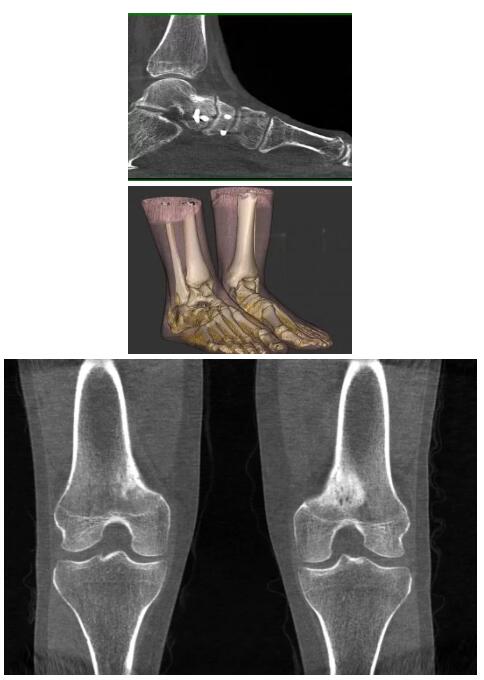

比如上面這款專用于足部和踝部掃查的CT成像系統(tǒng),患者在進行CT掃查時只需要站在上面即可,雙腳站或者單腳站都可以,當然,如果患者不是那么方便站著做完CT掃查,也可坐在上面。

而患者站著做足部或者踝部做CT檢查還有個好處是,可以檢查患者在負重的情況下,骨關節(jié)的真實情況,而躺著做CT掃查時未必能看出來。負重CT掃查特別是對于受傷的運動員或者舞蹈員來說意義更大,能夠更準確地評估傷情,幫助他們盡早復原。

以上介紹的CT均來自國外同一家公司,這些CT均配置了可視化軟件,可以進行切片、3D重建以及大型CT附帶的所有典型的操作功能。

以下是這些“特立獨行”的CT所拍出來的圖像: